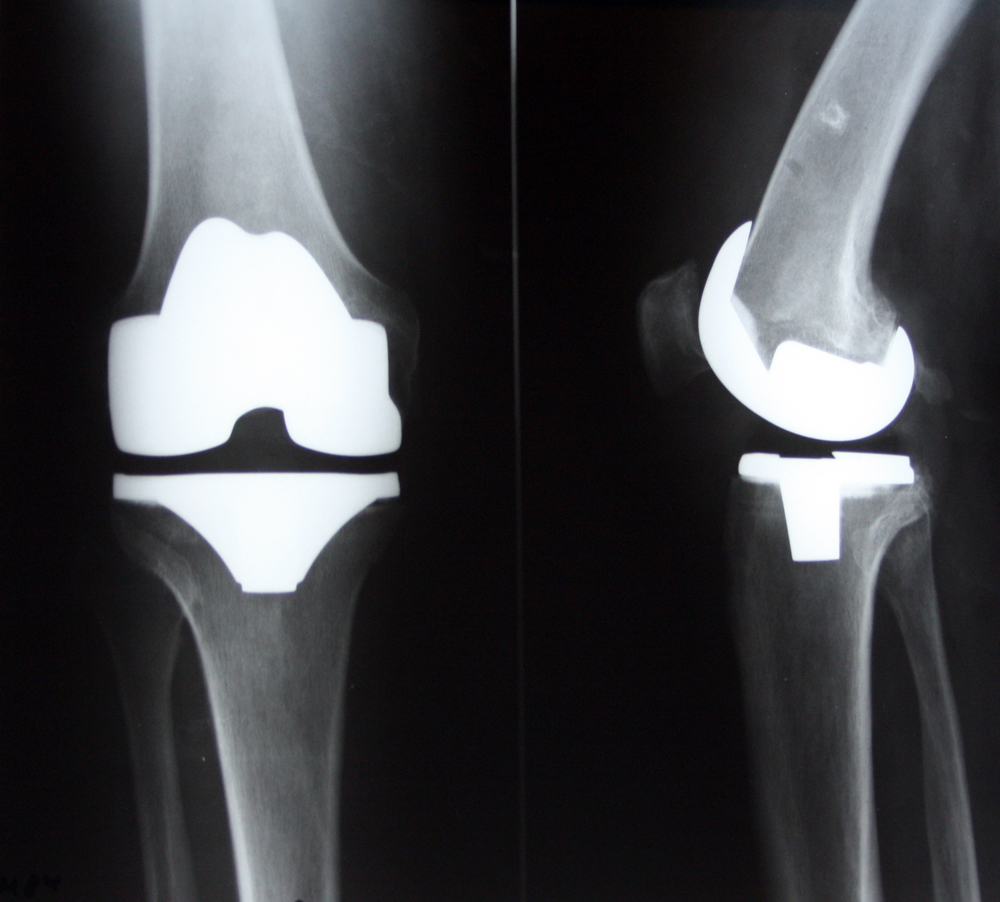

Среди множества методов хирургического лечения заболеваний крупных суставов - одним из самых эффективных является эндопротезирование — операция, во время которой поврежденный сустав заменяют эндопротезом. Результатом хирургического вмешательства является уменьшение боли, восстановление работоспособность сочленения и конечности, что позволяет существенно повысить качество жизни.

Операция характеризуется высокой эффективностью и низким (1-2%) риском осложнений.